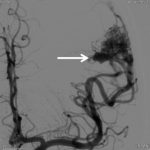

兩天後….在私家醫院為她做診斷式的動態腦血管造影來確定䐉血液的流動模式後,再進行了4 小時的顯微鏡手術….AVM的計時炸彈完全切除……..在AVM旁邊的腦部亦能看到血鐵黃素的舊有殘留血液。手術後兩天出院。